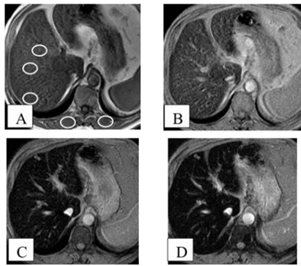

Observe as imagens a seguir.

Sobre a RM acima, de um paciente com hemocromatose, assinale a afirmativa correta.